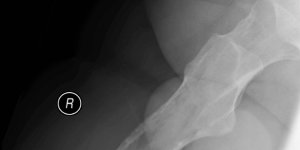

Plasmacytoma | Cases

Retrospective case study 66 Male 1 year history of right thigh pain Attended physiotherapy. Given exercises for tight thigh muscle. No improvement. Consulted GP 10-12 months after physiotherapy as he developed problems with sit to stand. GP requested X-ray pelvis. X-ray report as follows. GP referral for x-ray mentions – “Injury right leg two [...] Read more